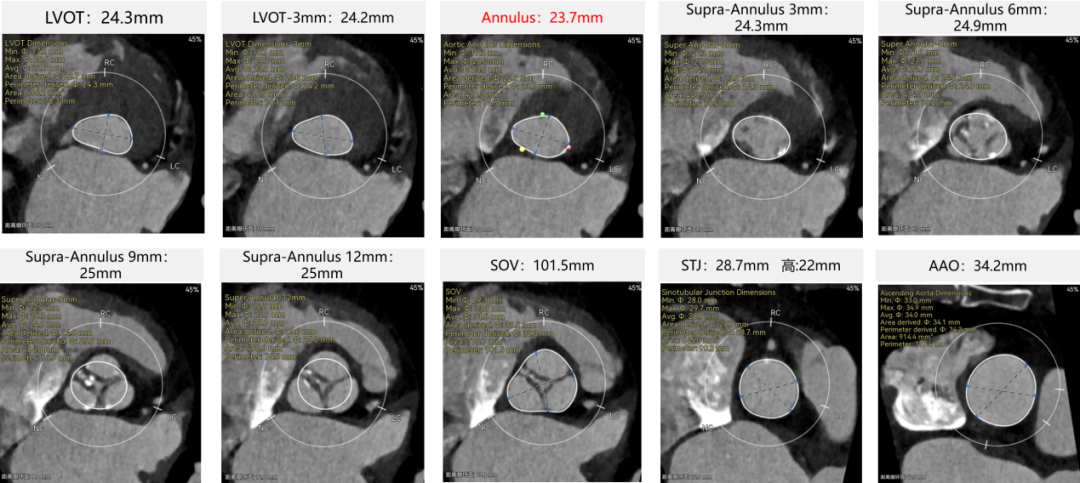

患者病史 术前超声提示:主动脉瓣退行性病变;中-重度狭窄并轻度返流;中-重度三尖瓣返流;中度肺高压 术前CT 三叶瓣,瓣叶增厚轻度钙化,右无交界有粘连,预计可以扩开,主动脉根部直径23.7mm,LVOT直径24.3mm,呈直筒型;双侧冠脉开口高度可,瓣叶长度小于冠脉开口上缘到主动脉根部的距离;窦部空间可,STJ、升主动脉内径可;主动脉水平夹角43.6°,非横位心;主动脉弓角、弓距可,左室内径可;外周入路无明显迂曲,有零星散状钙化,双侧股动脉内径可,均能通过20F大鞘,右股低分叉。 手术策略 推荐右侧股动脉为主入路使用20F大鞘,左侧股动脉为辅入路,右股分叉上方1cm穿刺;推荐使用22mm球囊预扩,预装AV26瓣膜,备AV29瓣膜,初始定位为真实瓣环上方3mm,瓣膜释放过程中释放张力使其自然下滑,工作位观察瓣膜稳定性,最终理想位置为零位;左右重合位:RAO23°CAU32°;右窦居中位:LAO5°CAU12°;左冠切线位:LAO34°CRA14°。 手术过程 术中右股动脉痉挛,内径变为3.8mm,遂更换左腋动脉入路;18球囊预扩,后植入AV26 ProStyle A®瓣膜;瓣膜精准释放于目标位置,超声显示无明显瓣周漏,血流动力学即刻改善。 术中右股动脉痉挛,内径变为3.8mm,更换左腋动脉 主动脉根部造影 18球囊预扩 初始定位 工作位观察 术后即刻表现:无瓣周漏,术后峰值压差10mmHg 术后3天复查超声峰值压差14mmHg Prostyle A®预装干瓣——助力临床最优化解决方案: 轻松过弓,精准可控:该病例经左腋动脉入路,输送系统较细的尺寸+柔顺的输送系统通过性能得到了很好的验证; 释放稳定:平衡的径向支撑力降低了释放过程中的张力,流入端小锥角设计能够迅速锚定贴边,80%可回收使得观察位和释放后的位置差距减少,大大提高了释放过程中的精准性,能够轻松应对高难度病例; 预装干瓣 便捷顺安:金仕生物专利抗钙化技术运用纳米技术去除组织内的细胞碎片和磷脂,封闭游离醛基,从根本上阻断了瓣膜钙化的多项因素,显著提升了瓣膜的耐久性;同时,相比较传统戊二醛保存方式,干式存储最大限度的保留心包的亲水亲油平衡,还原组织天然曲柔性,进一步保障了瓣叶开合,保证长期耐久性; 谢年谨教授 广东省人民医院 谢年谨教授指出:“对于外周血管条件较差的心脏瓣膜病患者,腋动脉路径凭借其更直接的解剖通路与更稳定的输送环境,为手术安全提供了重要保障,尤其适用于股动脉入路失败的复杂病例。该路径不仅能显著降低血管损伤、出血等并发症风险,还能通过更清晰的操作视野提升手术成功率;尤其在高龄、动脉硬化严重的患者群体中,腋动脉路径的适应性优势更为突出。 专家简介 荆志成 广东省人民医院 谢年谨 广东省人民医院 刘勇 广东省人民医院 · END ·